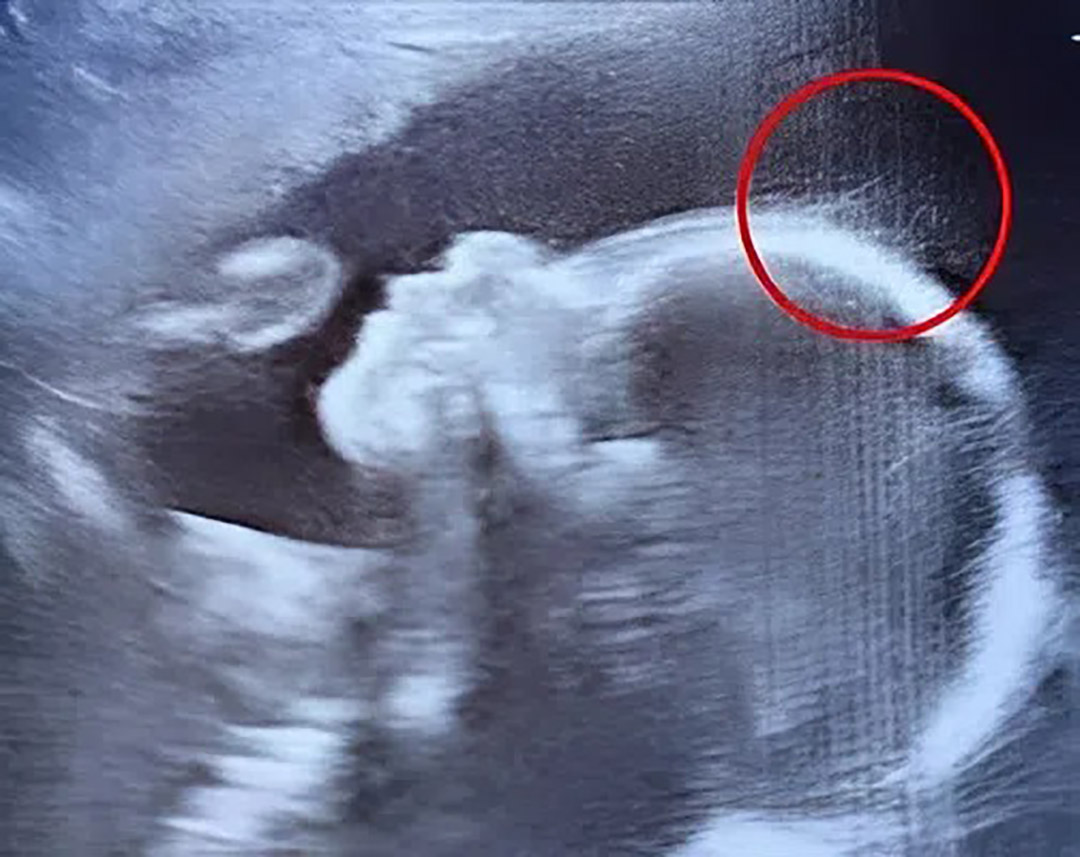

Ivy, une naissance remarquable : des cheveux visibles dès l’échographie

Lors d'un contrôle prénatal de routine, un détail inattendu a captivé l'attention du personnel soignant : une chevelure déjà discernable sur l'imagerie. Cette découverte insolite annonçait le début d'une aventure médicale fascinante qui allait marquer tous les témoins de cette grossesse hors du commun.